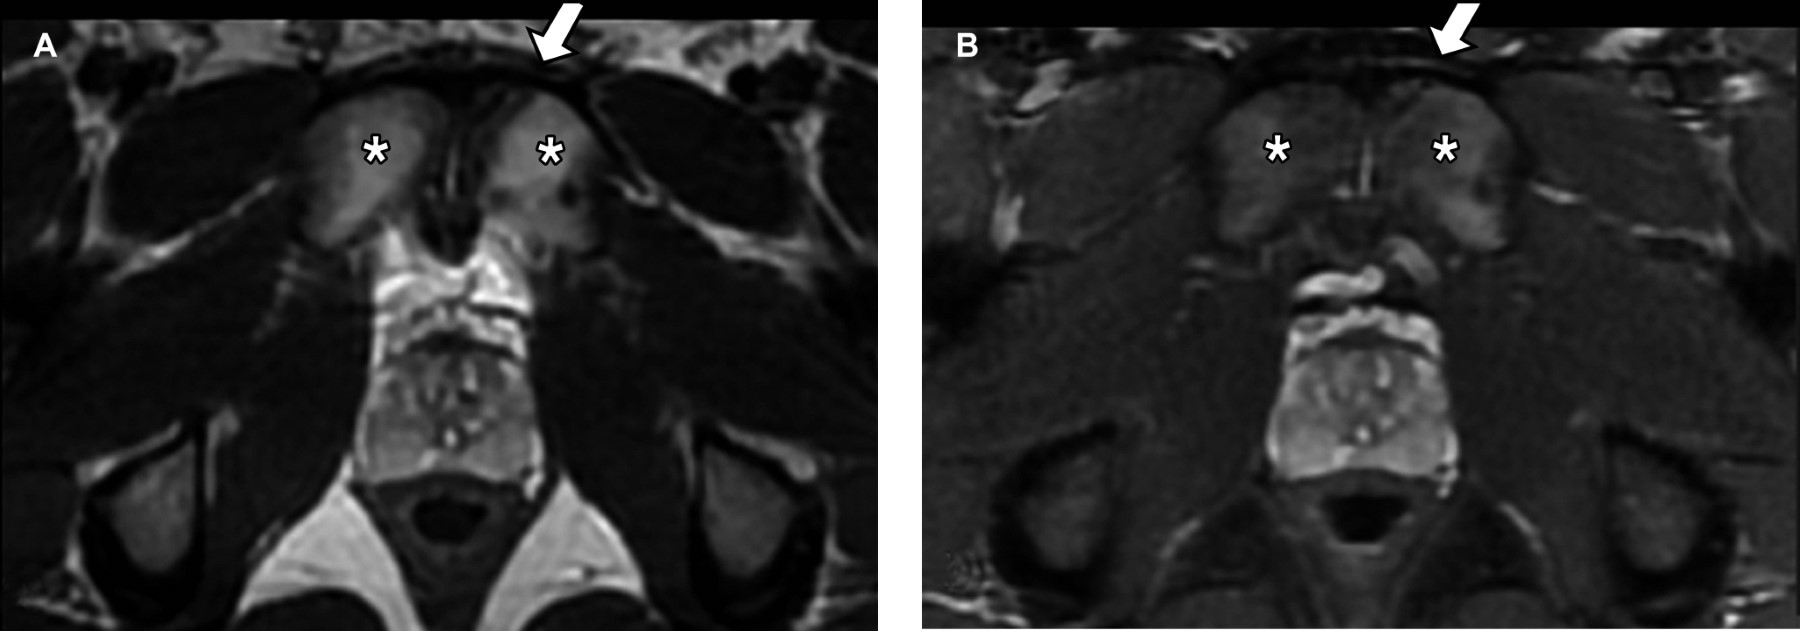

Athletic pubalgia is a clinical syndrome characterized by chronic inguinal pain secondary to muscle, tendon, or bone injury at the pubic bone level. It is a confusing diagnosis because there is a wide spectrum of pathologies that cause inguinal pain, and the clinical picture is nonspecific. In these patients, the magnetic resonance imaging (MRI) study plays a fundamental role in providing an accurate diagnosis.

Figure 1